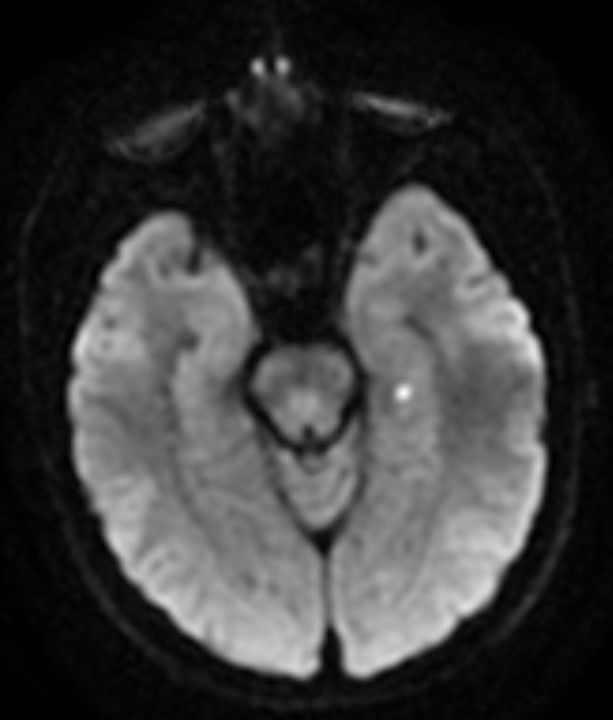

Image IQ Quiz: 57-Year-Old Female with Altered Mental Status

A 57-year-old female presents with an altered mental status. What do the images reveal?